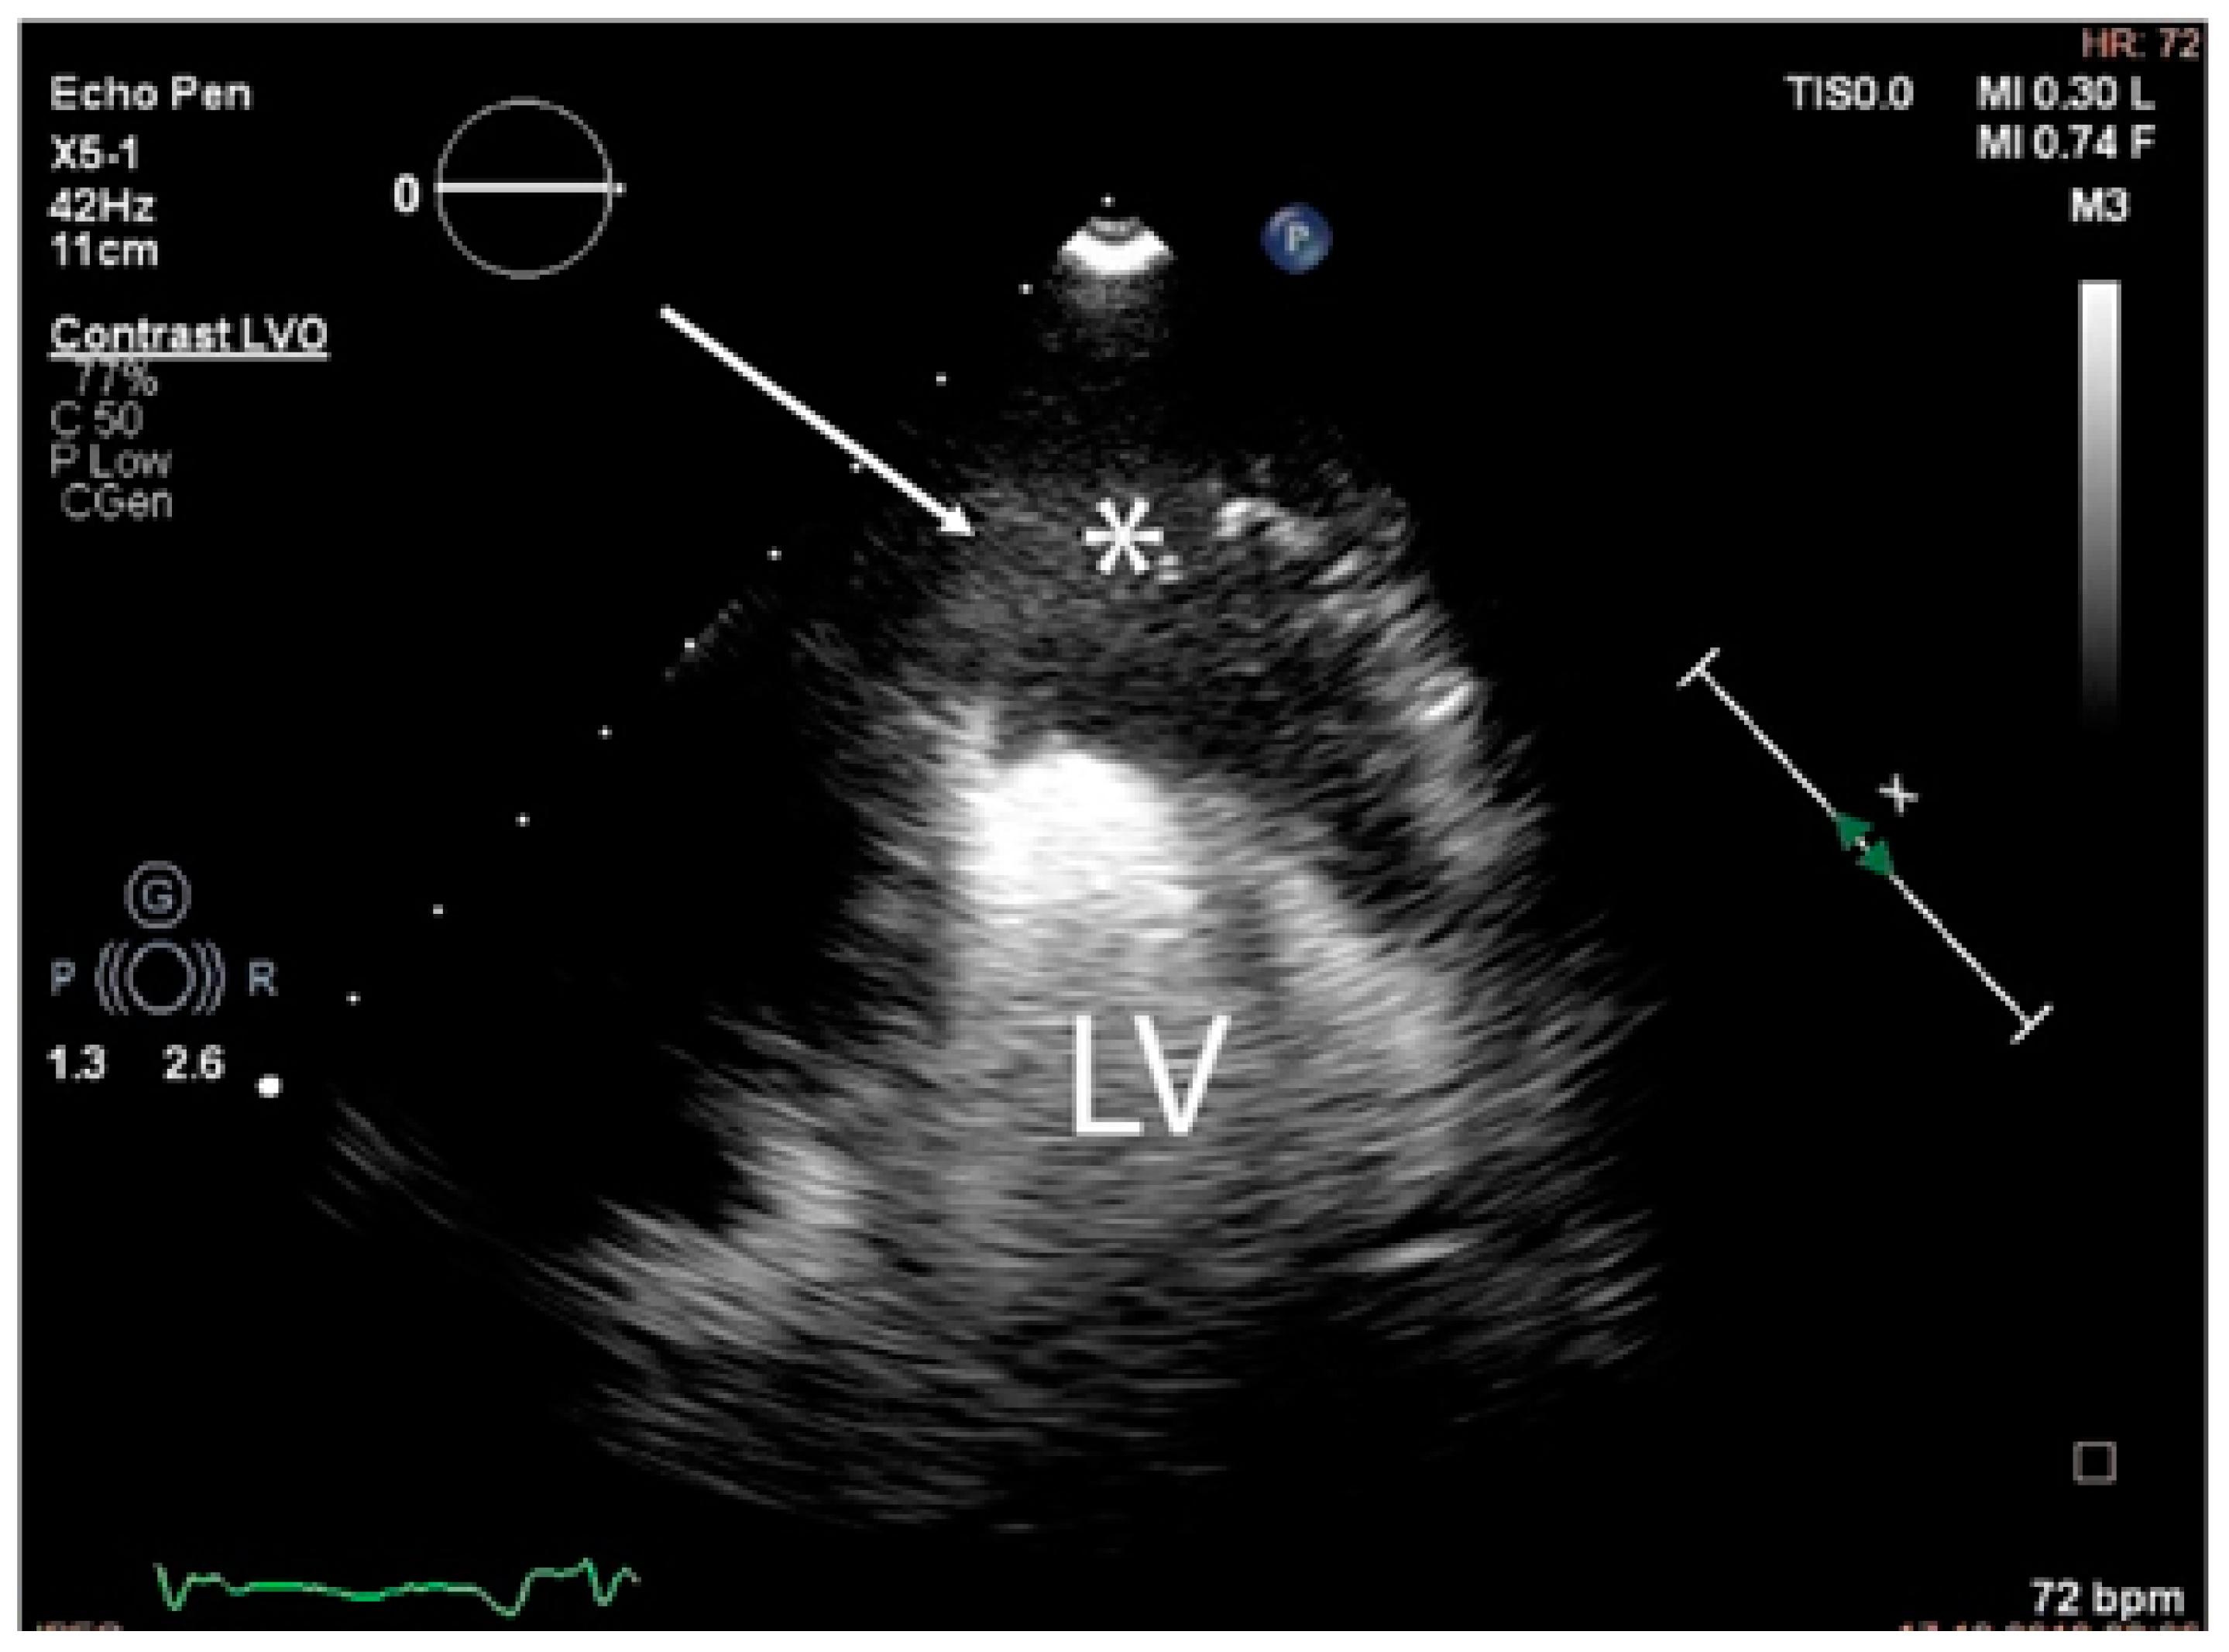

The troponin I level was found to be slightly elevated (90 ng/mL). Coronarography was used to rule out any luminal or anatomical abnormalities. A tumour filling the right ventricle and involving the apex of the left ventricle was identified at transthoracic echocardiography (Figure 3 and Figure 4).

The tumour size and degree of infiltration over the whole apex of the left ventricle were determined by injecting 2 mL of SonoVue (Bracco S.p.A., Milan, Italy) at the level of intra-myocardial contrast in the left ventricle. The presence of microbubbles at this level confirmed the vascularization of the tumour mass. A non-homogeneous right ventricular mass of 88/61/80 mm extending to the left ventricle with areas of necrosis in both ventricles, disseminated lobular nodules on both pulmonary fields measuring 9 mm (right lung), 17 mm (left lung), and right para-tracheal adenopathy were identified on a thoracic CT scan (Figure 5 and Figure 6).

Since surgery was contraindicated by the general status of the patient, a 3D ultrasound-guided biopsy of the tumour was performed. The anatomical landmarks for the cardiac biopsy were established by integrating CT and MRI data. Low contractility of the cardiac apex allowed for the biopsy to be conducted at this level (Figure 8).

A complex multidisciplinary team supervised the biopsy that was performed in the operating room. Transthoracic ultrasonography using a convex probe identified the apical tumour, the absence of hypo-echogenic left ventricle motility in contrast with the remaining myocardial wall, and the infiltration of the adjacent pericardium. The biopsy was performed via the left inferior parasternal route by using an ultrasound-guided 10 cm 20G coaxial biopsy needle inserted percutaneously. Three tumour fragments of 1 by 2 cm were obtained. No incidents were recorded during or after the procedure. Histological reports confirmed the presence of a high-grade primary intimal cardiac sarcoma with areas of myxoid differentiation and epithelioid-appearing cells (Figure 9).